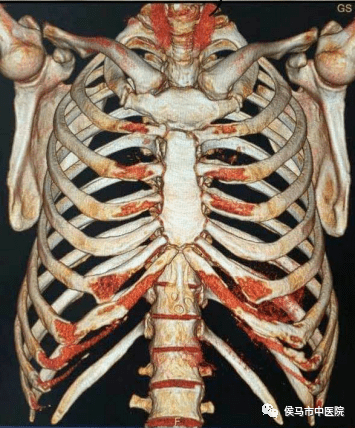

7、全身各部位骨三维重建

该设备强大的后处理软件,能对全身各部位骨三维立体快速成像,清晰显示骨结构的细微结构,对骨折及内固定显示清晰、直观,能更好地为临床服务。